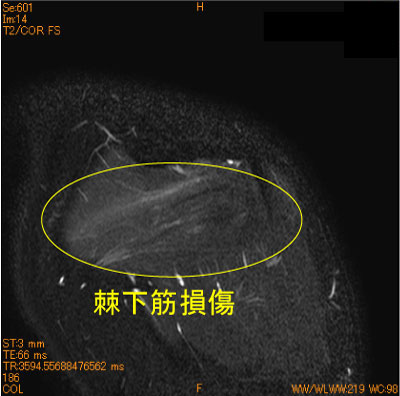

30代女性、バレーのレッスンで腕を内外旋すると疼痛出現。

棘下筋に筋挫傷を認めている。腱板断裂疑いであったが、腱板ばかり見ていると見落とす。

脂肪抑制T2WI は必ず必要である。

![]() Obl. Cor T2WI 脂肪抑制 |